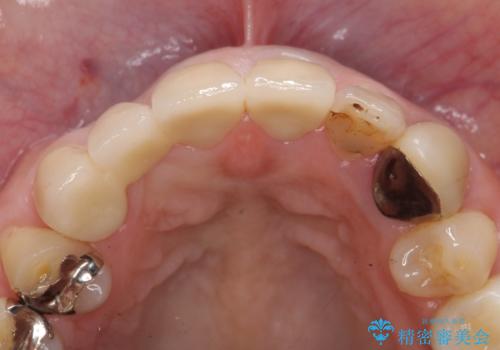

その後ブリッジによる補綴を行うことで、自然な見た目を再現することができました。

前歯の補綴ではオールセラミッククラウンを希望される患者様が多いですが、オールセラミッククラウンの中でも、エコノミー、スタンダード、スペシャル、エクセレントとランクがあります。

その中でも特に審美性が高いのがスペシャル、エクセレントです。スペシャル、エクセレントは口腔内写真をもとに熟練の技工士が、患者様の口腔内に合わせたオーダーメイドのクラウンを製作致します。